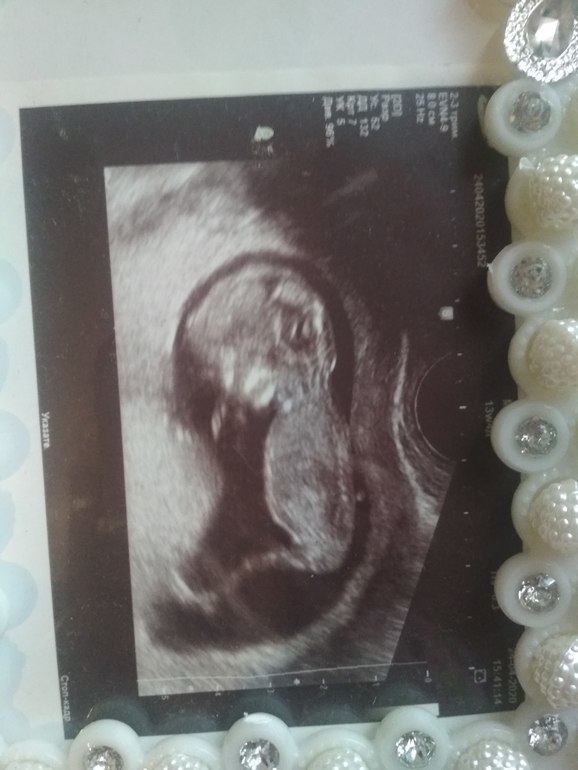

Наше второе узи, помогите по фото определить пол))

УЗИ, КТГ, доплерДевочки,была на втором плановом узи!С нашей бусинкой все в порядке,все соответствует сроку: положение плода продольное, бпр 46мм, ог 169мм,ож 137 мм, дб 29мм, плацента по передней стенке 23 мм, нормальная. Количество вод нормальное, длина ш/матки 40мм, вес плода 270 г. Единственное не указали ктр...Беременность 19нед.3 дня. И нам предположили(правда совсем неуверенно) девочку! Дорогие мои,посмотрите пожалуйста,хотелось бы все-таки знать наверняка)Очень уж хочется начать делать приятные покупочки)))

Мне кажется у вас девочка, у нас почти такой же снимок, я сама в замешательстве кто...

на девочку больше похоже (хотя и узисты и мы все можем ошибаться), лучше универсальный цвет для первых покупок выбирать — чтобы и мальчику и девочке пригодились. На будущее точно ещё пригодится!!!